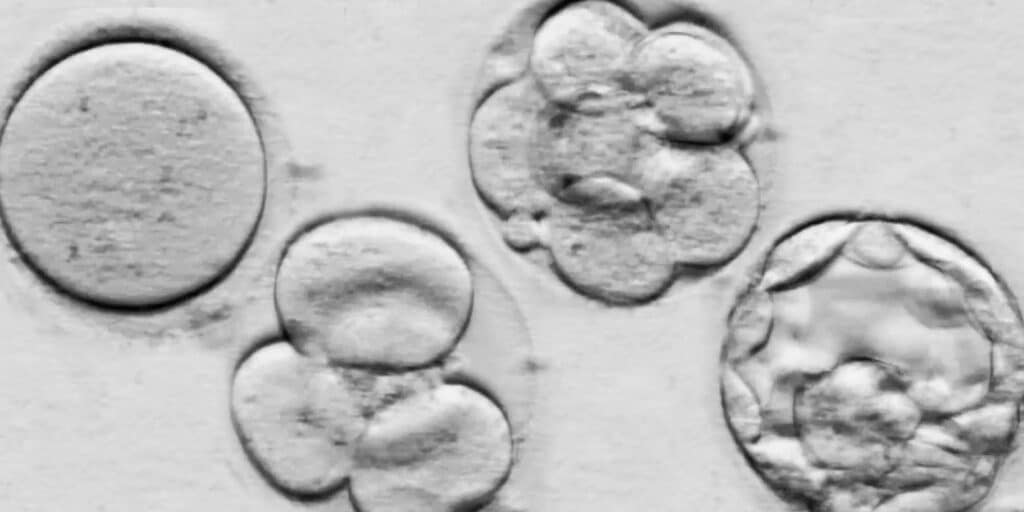

Uma das opções mais comuns é a fertilização in vitro (FIV), na qual os óvulos são coletados dos ovários da mulher ou de uma doadora, fertilizados em laboratório com espermatozoides e os embriões resultantes são transferidos para o útero da paciente. A FIV é uma técnica altamente complexa e eficaz, podendo superar os desafios relacionados à redução da reserva ovariana após a quimioterapia.

Outra alternativa é o uso de óvulos doados, que pode ser uma possível solução para mulheres que não possuem óvulos viáveis ​​após o tratamento de câncer. Nesse caso, os óvulos de uma doadora saudável são fertilizados em laboratório com o esperma do parceiro ou de um doador e os embriões resultantes são transferidos para o útero da paciente.

Uma das opções mais comuns é o congelamento de óvulos, na qual os óvulos da paciente são coletados, fertilizados em laboratório e congelados para uso posterior em procedimentos de fertilização in vitro (FIV). Esse procedimento oferece possibilidade de preservar a fertilidade antes que a quimioterapia possa afetar a reserva ovariana e a qualidade dos óvulos da paciente.